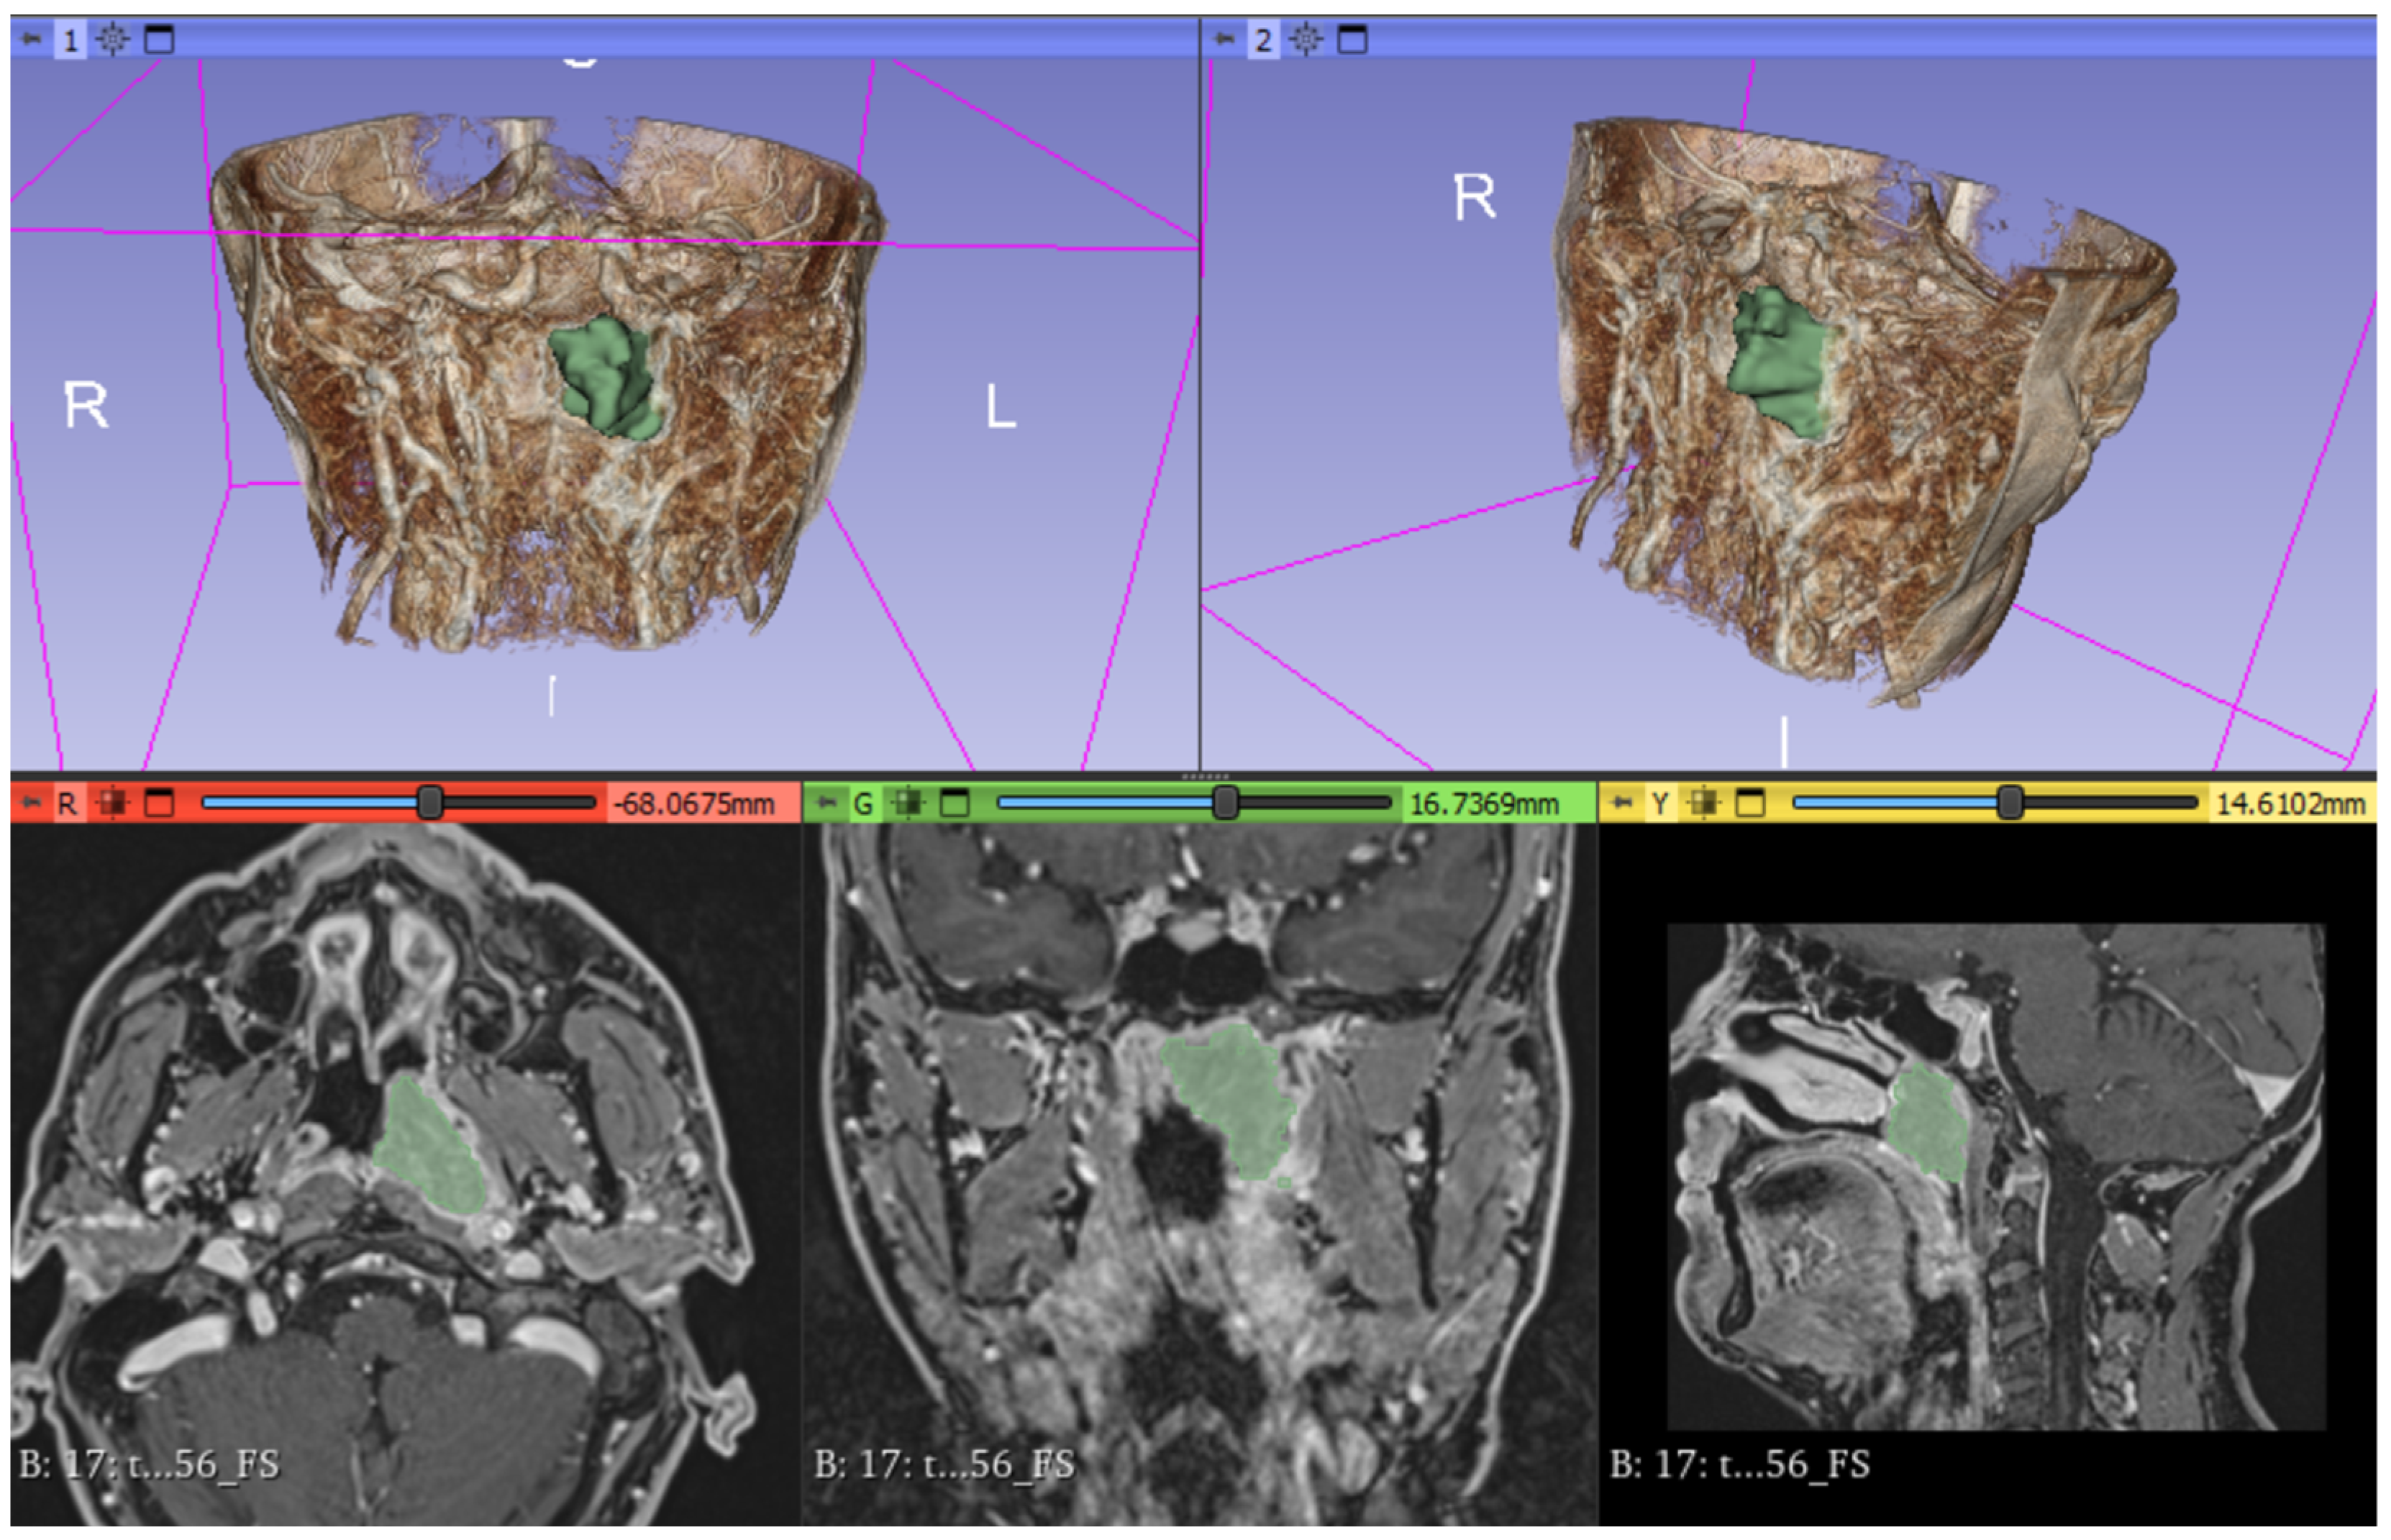

From pre-treatment MRI scans, the entire volume of the lesion was segmented on both ADC maps and post-gadolinium T1w sequences by employment of the open-source software 3DSlicer (software version 4.10.2, https://www.slicer.org/ accessed on 18 December 2023). The ROI (region of interest) was delineated slice-by-slice for each patient by a radiologist with an experience of over 5 years in head and neck pathology (Figure 2).

Figure 2.

Segmentation of the lesion on 3D Slicer software. The volume of interest (VOI) is traced in green. The 3D render shows tumor mass in green.